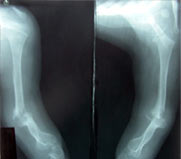

Cubitusvarus

Cubitus Varus -x-ray